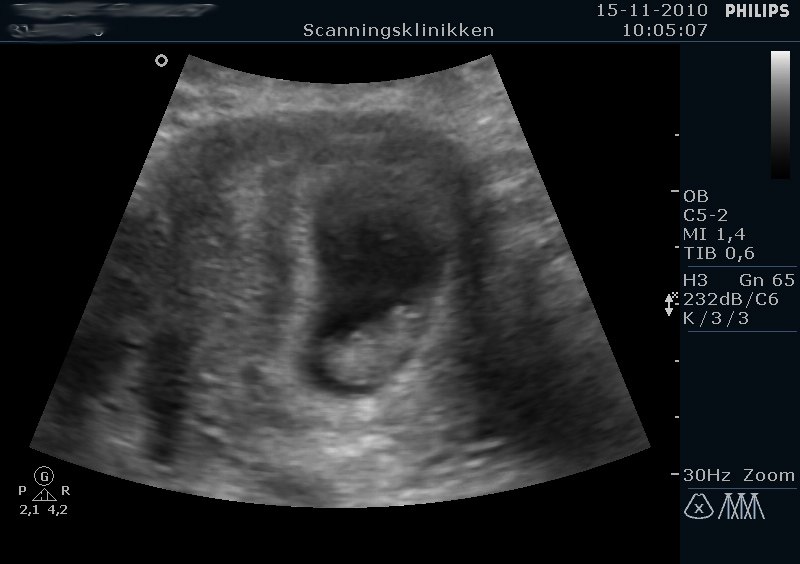

Så har jeg været til tidlig scanning. Alt var i skønneste orden, og jeg fik ros for en fin babyhule. Moderkage så ud til at blive dannet bagtil, så jordmor mente at jeg ville mærke liv tidligt.

Hun kunne dog måle at jeg ikke var 9+6 men istedet 8+5. Hun beroligede mig dog, og sagde at med så fint hjerteblink og fin lille spunk, skulle jeg ikke gå og være nervøs frem til 12. uge. Skønt !!

Neders ser I spunken, og på det ene billede er der foroven i det "sorte hulrum" en lille rund prik. Det er blommesækken, som spunken lever af indtil 11. uge ca. Sjovt.